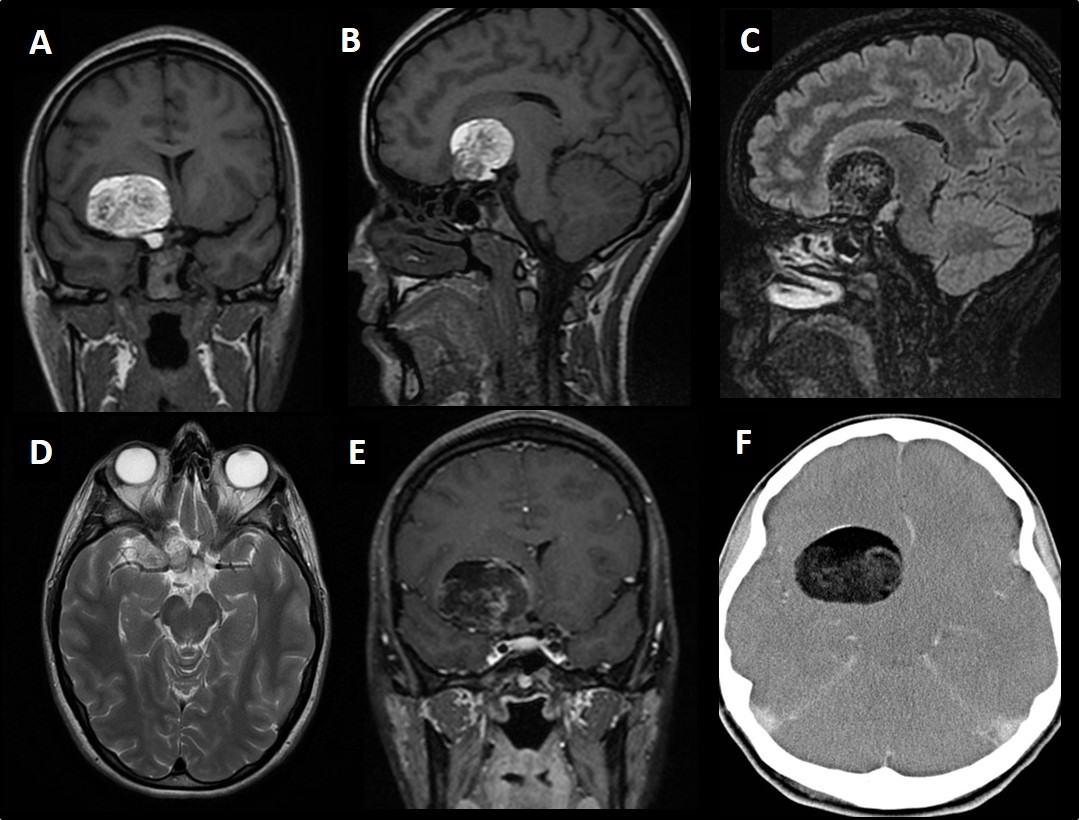

Caso del mes Octubre 2017

« Todos los casosAutores Dra. Jimena Angarita Beltrán. Servicio de Radiodiagnóstico, Complejo...